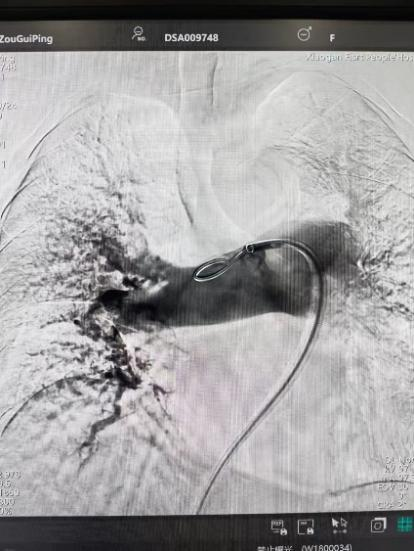

術(shù)前

手術(shù)在局部麻醉下進(jìn)行,團(tuán)隊(duì)通過(guò)股靜脈穿刺,將專(zhuān)用抽栓導(dǎo)管精準(zhǔn)送達(dá)肺動(dòng)脈栓塞部位,利用負(fù)壓抽吸技術(shù)成功清除大量血栓;隨后,在血栓局部精準(zhǔn)灌注溶栓藥物,進(jìn)一步溶解殘余血栓,恢復(fù)肺部血流灌注;同時(shí),為防止下肢深靜脈血栓再次脫落引發(fā)肺栓塞,團(tuán)隊(duì)為患者置入下腔靜脈濾器,整個(gè)手術(shù)歷時(shí)約1小時(shí)。術(shù)后,鄒婆婆呼吸困難癥狀即刻得到緩解,血氧飽和度顯著提升,右心負(fù)荷明顯減輕,目前身體狀況正在逐步恢復(fù)中。